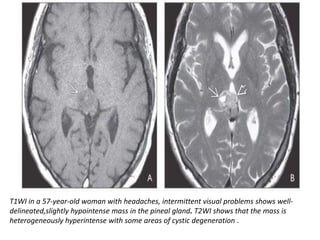

T1WI in a 57-year-old woman with headaches, intermittent visual problems shows well-

delineated,slightly hypointense mass in the pineal gland. T2WI shows that the mass is

heterogeneously hyperintense with some areas of cystic degeneration .

Moderate heterogeneous enhancement is seen on T1 C+. MRS shows elevated Cho , decreased

NAA , lactate doublet . Pineal parenchymal tumor of intermediate differentiation, WHO grade

II, was diagnosed on imaging and confirmed at histopathology